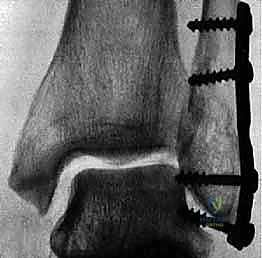

المرحلة الثالثة: رد العظام وتثبيت الكعب الوحشي (الشظية)

يبدأ الجراح عادة بإصلاح الشظية لأنها تعتبر "العمود الفقري" لاستقرار الكاحل. يتم إرجاع قطع العظم إلى مكانها التشريحي الطبيعي (الرد المفتوح). ثم يتم تثبيتها باستخدام شريحة معدنية (Plate) ومجموعة من المسامير (Screws) لتثبيتها بقوة.

المرحلة الرابعة: تثبيت الكعب الإنسي (الظنبوب)

بعد استقرار الجانب الخارجي، ينتقل الجراح للجانب الداخلي. يتم تنظيف منطقة الكسر من أي أنسجة محشورة، ثم يتم رد الكعب الإنسي وتثبيته غالباً باستخدام مسمارين طويلين (Cancellous screws) أو تقنية الأسلاك والشد (Tension band wiring) حسب شكل الكسر.